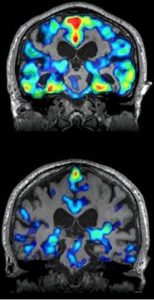

Cortisol blokkeert je vetverbranding en diëten vertraagd je metabolisme.

Dit komt niet door te weinig wilskracht, maar te veel cortisol

Als je gewicht niet past bij wie je bent, is de oorzaak vaak te hoog cortisol. Dat verhoogt je bloedsuiker. Je lichaam wordt klaargemaakt om te vechten of te vluchten.

Je kunt daardoor zelfs aankomen, zonder te eten!

Overgewicht door cortisol herken je aan het buikvet. Dat is wat begint met opblazen, daarna je gezicht en later vaak je bovenarmen. Daarnaast gaat het vaak gepaard met veel andere klachten. Denk aan ontstekingen, opgejaagd gevoel, zorgen, auto-immuun aandoeningen en vermoeidheid etc. Deze hormonale disbalans, wordt bovendien rond de overgangsperiode, meestal erger.